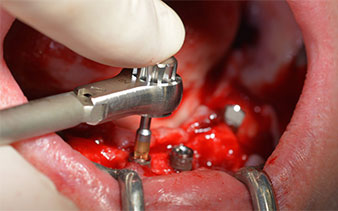

The surgical protocol for the implants employed (SKY, bredent medical) specifies a speed of 1,200 rpm for the pilot drilling (Fig. 7 - 9).

speed of 1,200 rpm

This corresponds to the next preset position in the Implantmed. Here we see the W&H contra-angle handpiece being held at a 45° angle to mesiocaudal in the region of 45 in order to preserve the mental nerve. The mental foramen is used as the anatomic reference for all drilling in this region. The subsequent holes were drilled at a reduced speed of 300 rpm (Fig. 10 and 11).

W&H contra-angle